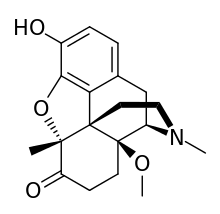

The pharmacodynamic response to an opioid depends upon the receptor to which it binds, its affinity for that receptor, and whether the opioid is an agonist or an antagonist. For example, the supraspinal analgesic properties of the opioid agonist morphine are mediated by activation of the μ1 receptor; respiratory depression and physical dependence by the μ2 receptor; and sedation and spinal analgesia by the κ receptor. Each group of opioid receptors elicits a distinct set of neurological responses, with the receptor subtypes (such as μ1 and μ2 for example) providing even more [measurably] specific responses. Unique to each opioid is its distinct binding affinity to the various classes of opioid receptors (e.g. the μ, κ, and δ opioid receptors are activated at different magnitudes according to the specific receptor binding affinities of the opioid). For example, the opiate alkaloid morphine exhibits high-affinity binding to the μ-opioid receptor, while ketazocine exhibits high affinity to ĸ receptors. It is this combinatorial mechanism that allows for such a wide class of opioids and molecular designs to exist, each with its own unique effect profile. Their individual molecular structure is also responsible for their different duration of action, whereby metabolic breakdown (such as N-dealkylation) is responsible for opioid metabolism.

Several semi-synthetic opioids were developed in Germany in the 1910s. The first, oxymorphone, was synthesized from thebaine, an opioid alkaloid in opium poppies, in 1914.[228] Next, Martin Freund and Edmund Speyer developed oxycodone, also from thebaine, at the University of Frankfurt in 1916.[229] In 1920, hydrocodone was prepared by Carl Mannich and Helene Löwenheim, deriving it from codeine. In 1924, hydromorphone was synthesized by adding hydrogen to morphine. Etorphine was synthesized in 1960, from the oripavine in opium poppy straw. Buprenorphine was discovered in 1972.[228]